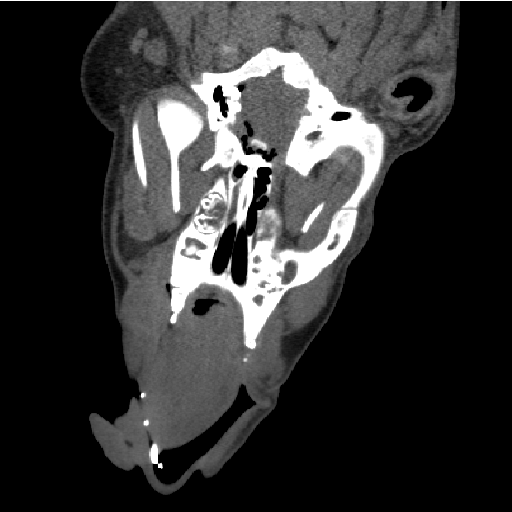

A CT coronal view of a pig.